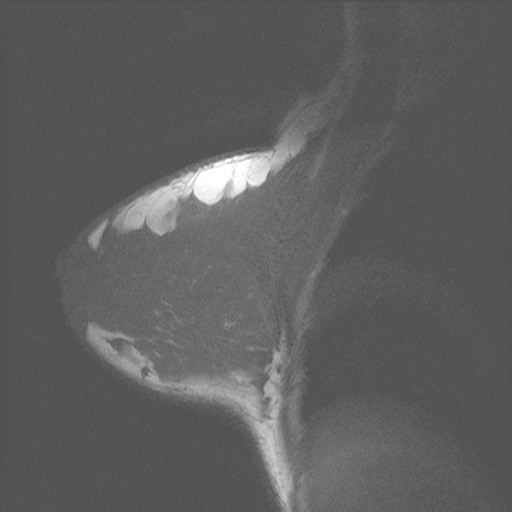

borst